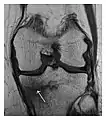

High-energy trauma fractures

Occult osseous injuries may result from a direct blow to the bone by compressive forces of adjacent bones against one another or by traction forces during an avulsion injury. Lesions in the tibial plateau, hip, ankle, and wrist are often missed. In a tibial plateau fracture, any disruption of the posterior and anterior cortical rims of the plateau should be sought. Impaction of subchondral bone will appear as an increased sclerosis of the subchondral bone (Figure 1). In the hip, posterior acetabular fractures also present subtle radiographic findings. The acetabular lines should then be carefully examined keeping in mind that the posterior rim, which is harder to see on X-rays, is more frequently fractured than the anterior rim (Figure 2). In the wrist, detection of carpal bone fractures is often challenging, with up to 18% of scaphoid fractures radiographically occult. Carpal fractures, especially the scaphoid, are associated with the risk of avascular necrosis. In apparently normal wrist radiographs from symptomatic patients, if there is history of a fall on an outstretched hand with pain in the anatomic snuffbox, suggesting scaphoid injury, the initial examination with posteroanterior, lateral, and pronation oblique views must be complemented by other specific views such as supination oblique and the "scaphoid" view A careful examination of cortices for evidence of discontinuity or offset and cancellous bone for lucency is necessary (Figure 3).[1]

Figure 1: A 56-year-old woman presenting with left knee pain after a fall. (a) Initial anteroposterior radiograph was considered normal, however, subtle cortical disruption of the anterior rim of the medial tibial plateau, medial to the tibial spine, is noted (arrow). (b) Coronal T1-weighted MRI confirms the cortical disruption (arrow) and shows extensive fracture through the proximal tibia. (c) Coronal proton density-weighted image with fat saturation shows extensive edema in the subchondral bone. Note also hypersignal adjacent to the medial collateral ligament corresponding to a grade I sprain (arrowheads).[1]